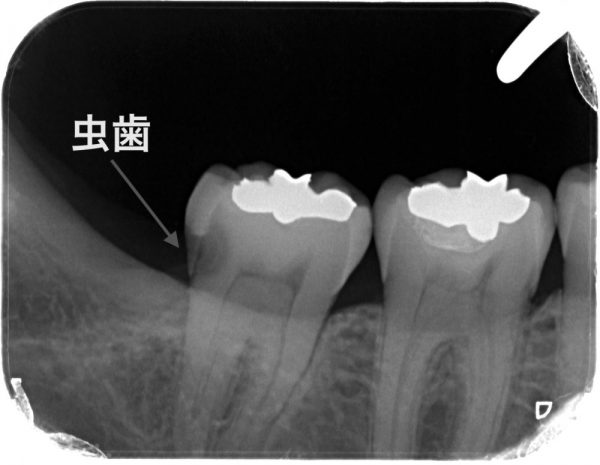

これは別の症例です。

親知らずはすでに抜いていますが、虫歯が進行しています。歯の内部に黒い線がありますが、これは神経の管です。神経の管の近くまで虫歯がきています。 一般的な虫歯治療だと、このように道具は前からしか入れることはできないので、大きく歯を削ることになります。虫歯は奥の黒いところだけなのに上部の健康な歯も大きく削ることにもなります。

一般的な虫歯治療だと、このように道具は前からしか入れることはできないので、大きく歯を削ることになります。虫歯は奥の黒いところだけなのに上部の健康な歯も大きく削ることにもなります。

しかも、神経の管を傷つけることも多く、神経をとる場合もあります。大きく歯を削ると神経をとるリスクも増えます。